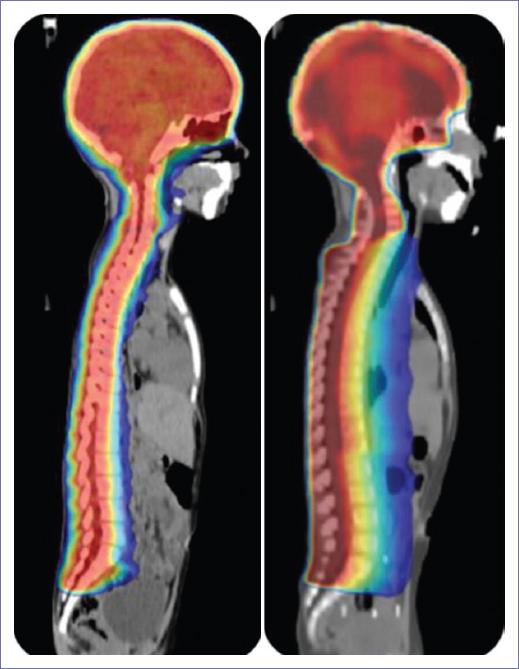

En la figura 1 se muestra la comparación de las técnicas de tratamiento; se observa una mayor conformación de la dosis al volumen cráneo-espinal en el plan realizado con VMAT. En la figura 2 se muestra la homogeneidad de distribución de la dosis en columna.

Figura 1 Tomografías en corte sagital en posición supina. Se muestra la distribución de las curvas de dosis en plano lineal. El color rojo representa el 100% y el azul, el 50. La imagen derecha corresponde a la técnica conformada y la izquierda a VMAT.